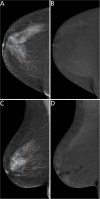

Objectives: To evaluate the potential of contrast-enhanced mammography (CEM) for reducing the biopsy rate of screening recalls.

Results: Between January 2019 and July 2021, 220 women were enrolled, 207 of them (median age 56.6 years) with 225 suspicious findings analysed. Three of 207 patients (1.4%) developed mild self-limiting adverse reactions to iodinated contrast agent. Overall, 135/225 findings were referred for biopsy, 90/225 by both SA and rCEM, 41/225 by SA alone and 4/225 by rCEM alone (2/4 being one DCIS and one invasive carcinoma). The rCEM biopsy rate (94/225, 41.8%, 95% CI 35.5-48.3%) was 16.4% lower (p < 0.001) than the SA biopsy rate (131/225, 58.2%, 95% CI 51.7-64.5%). Considering the 124/135 biopsies with final histopathology (44 benign, 80 malignant), rCEM showed a 93.8% sensitivity (95% CI 86.2-97.3%) and a 65.9% specificity (95% CI 51.1-78.1%), all 5 false negatives being ductal carcinoma in situ detectable as suspicious calcifications on low-energy images.

Conclusions: Compared to SA, the rCEM-based work-up would have avoided biopsy for 37/225 (16.4%) suspicious findings. Including low-energy images in interpretation provided optimal overall CEM sensitivity.

Key points: • The work-up of suspicious findings detected at mammographic breast cancer screening still leads to a high rate of unnecessary biopsies, involving between 2 and 6% of screened women. • In 207 recalled women with 225 suspicious findings, recombined images of contrast-enhanced mammography (CEM) showed a 93.8% sensitivity and a 65.9% specificity, all 5 false negatives being ductal carcinoma in situ detectable on low-energy images as suspicious calcifications. • CEM could represent an easily available one-stop shop option for the morphofunctional assessment of screening recalls, potentially reducing the biopsy rate by 16.4%.